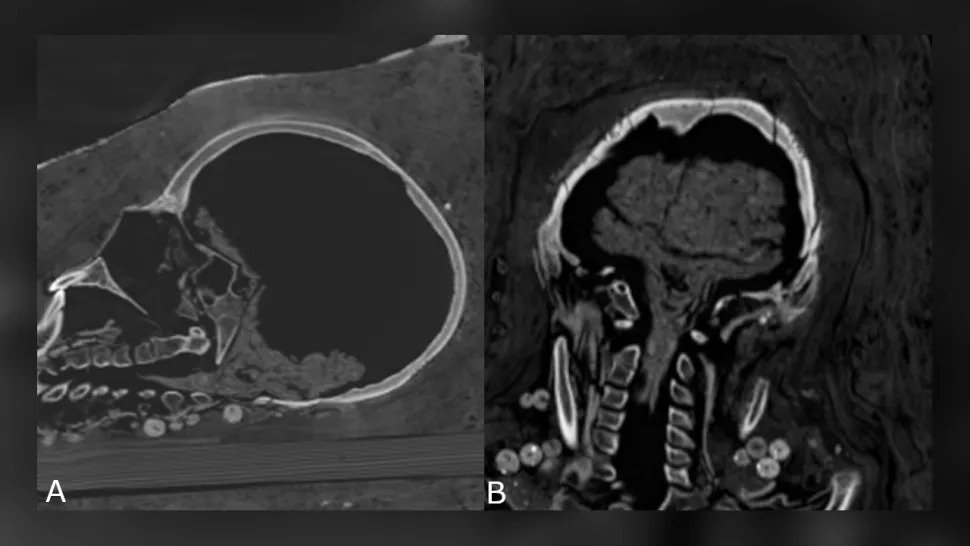

Anche il cervello della donna non è stato preservato, ma il cervello dell'adolescente è stato preservato – si era ridotto, ma il cervello e il tronco cerebrale potevano ancora essere identificati – ed erano presenti anche altri organi interni dell'adolescente.

Restringimento del cervello adolescente. (Zesh et al., PLOS One, 2020)

La donna, morta tra i 30 ei 40 anni, era alta circa 151 cm e aveva un'artrite avanzata al ginocchio sinistro. L'adolescente, secondo la tomografia computerizzata, è morto tra i 17 ei 19 anni ed era alto circa 156 cm.

Aveva un tumore benigno alla colonna vertebrale noto come emangioma vertebrale, che è più comune nelle persone sopra i 40 anni, hanno detto i ricercatori.